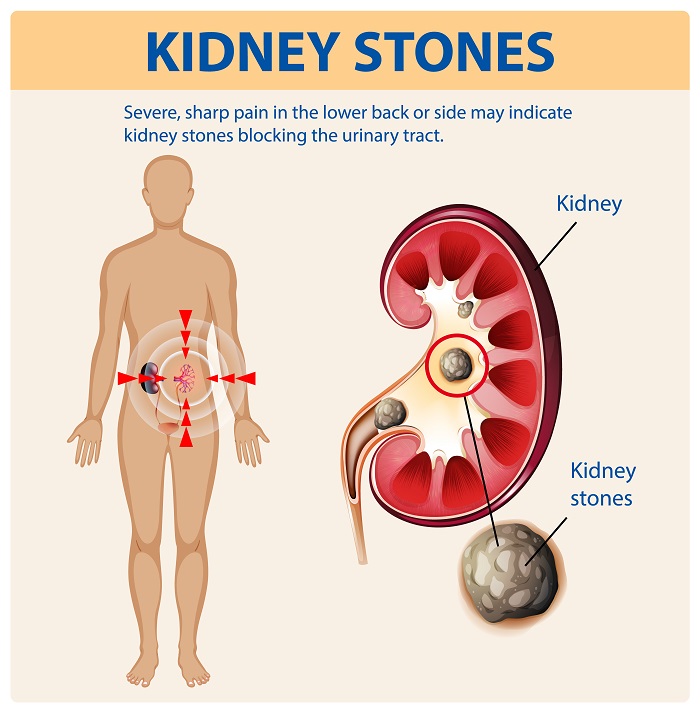

Understanding Kidney Stones and Why They Become Serious

Large Kidney Stones That Cannot Pass Naturally

Large stones often get stuck in the kidney or ureter, making natural passage difficult. Therefore, procedures like Kidney Stone Surgery in Raipur become necessary.

Recurrent Stone Formation and Chronic Pain

Repeated stone formation can damage the urinary system over time. Additionally, it can lead to ongoing discomfort and reduced quality of life.

Blockage in Urinary Flow and Infection Risk

When stones block urine flow, bacteria can grow, increasing the risk of infection. This condition may require urgent Stone Removal Surgery in Raipur.

Failed Previous Treatments Like Medication or ESWL

If medications or shockwave therapy do not work, PCNL Treatment in Raipur becomes the most effective option for complete stone removal.